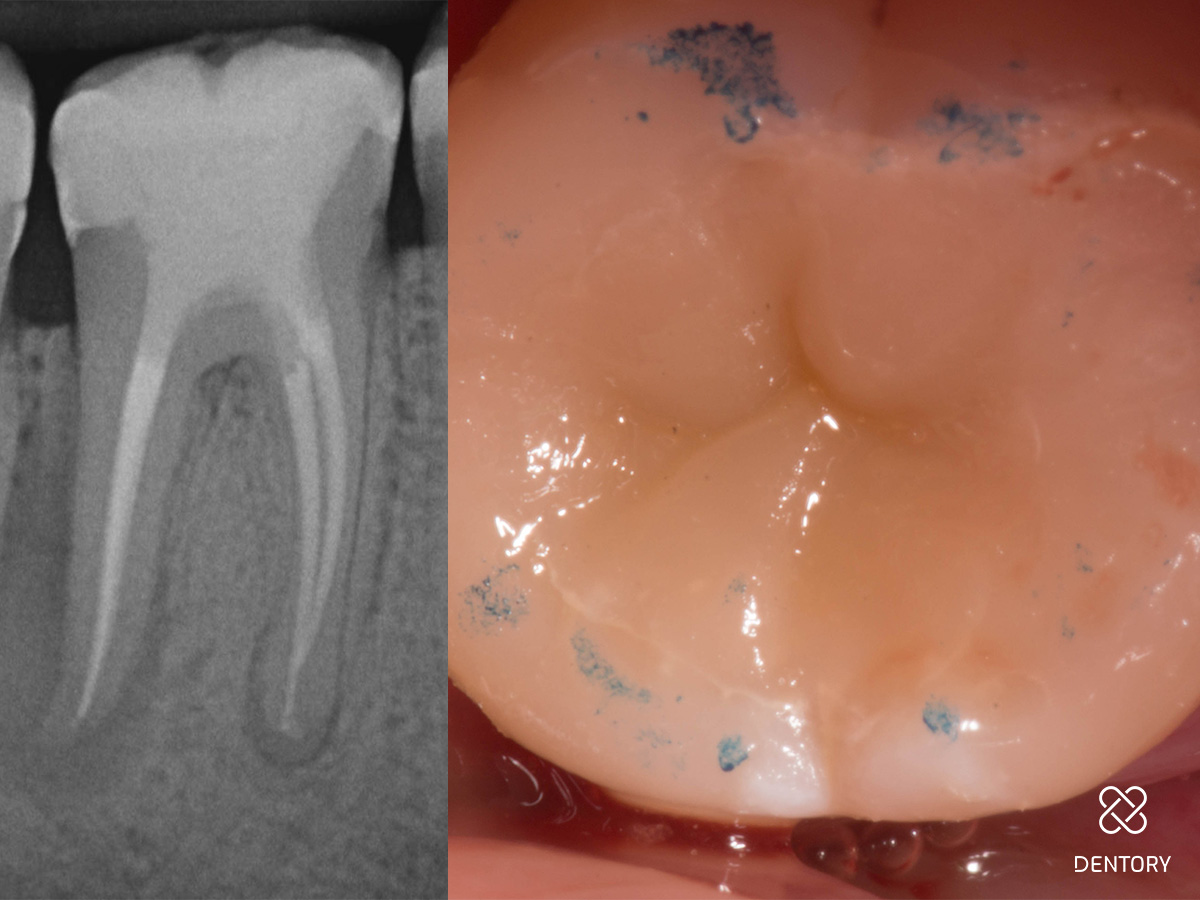

Abbildung 1

Ausgangssituation: Das initiale Röntgenbild zeigt den Grund für die Schwellung.

Abbildung 14

Wurzelfüllung-Kontrollaufnahme und Okklusionskontrolle.